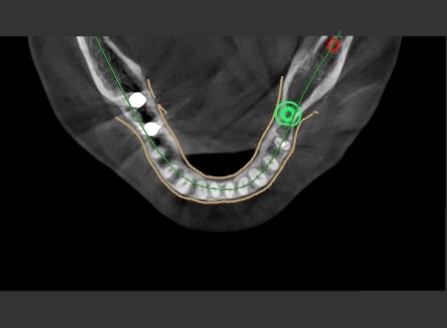

디지털(네비게이션) 임플란트 분석 1

디지털(네비게이션) 임플란트 분석 3

컴퓨터 분석을 토대로 가이드를 만들어

디지털 임플란트 를 심어 드렸습니다.